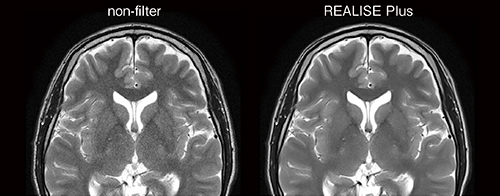

画像のノイズ信号を除去する高画質化ソリューションREALISE Plusは,複数のノイズ除去法を組み合わせ,受信信号とノイズの比であるSNRを最大 46%向上させることで,高画質化を実現する技術である(図3)。IP-RAPIDの進化に加え,REALISE Plusも搭載することで,SynergyDriveがない従来検査と比べて最大67%の撮像時間の短縮を実現した。

図3 高画質化ソリューションREALISE Plus

複数のノイズ除去法を組み合わせSNRが向上するため,画質改善が期待できる。